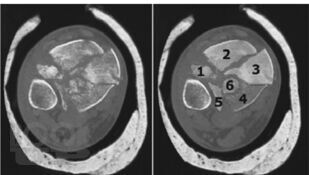

Современные принципы диагностики и лечения внутрисуставных переломов дистального отдела большеберцовой кости (переломы «пилона»)

Данное учебное пособие содержит подробное описание диагностики и тактики лечения переломов дистального метаэпифиза большеберцовой кости и возможности применения внеочагового и накостного методов лечения при данных видах переломов, а также описание послеоперационного ведения больных с данной патологией, возможные осложнения и сроки реабилитации после этого вида травмы.